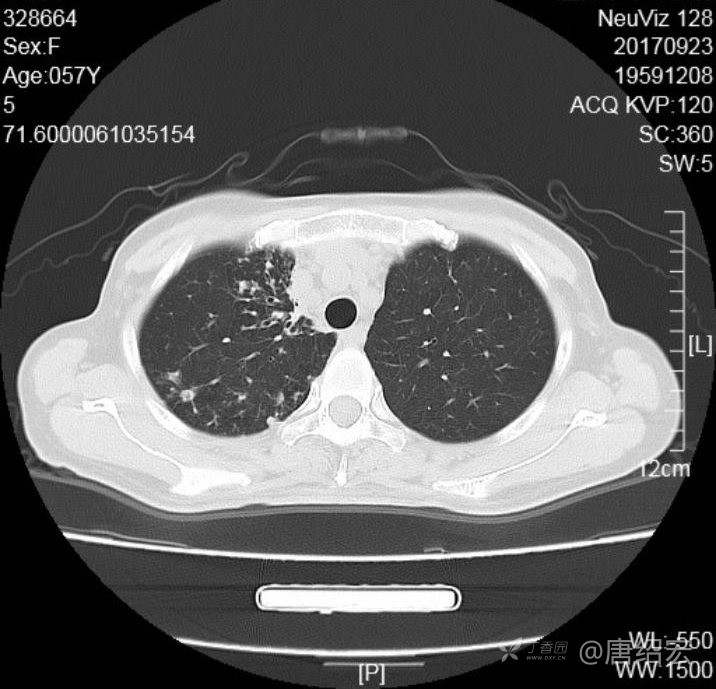

女,57岁,

主诉:发热、咳嗽、咯黄痰,胸闷3天入院。

铜绿假单胞菌性肺炎 (12)

铜绿假单胞菌感染 (20)